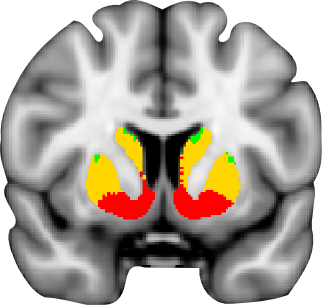

Oxford-GSK-Imanova structural and connectivity striatal atlases

A probabilistic atlas of sub-striatal regions, segmented according to their white-matter connectivity to cortical areas. This connectivity atlas reports anatomical connection from points in the striatum to each of 7 cortical zones obtained using probabilistic diffusion tractography in multiple subjects. For more details see the Striatal Connectivity Atlas web page.

Structural atlas

Atlas of sub-striatal regions, segmented according to the anatomical structure. Striatum is divided into caudate, putamen and ventral striatum according to the guidelines described by Tziortzi et al (2011). The sub-regions were manually delineated on the non-linear MNI152 template. For more details see the Structural Striatal Atlas web page.